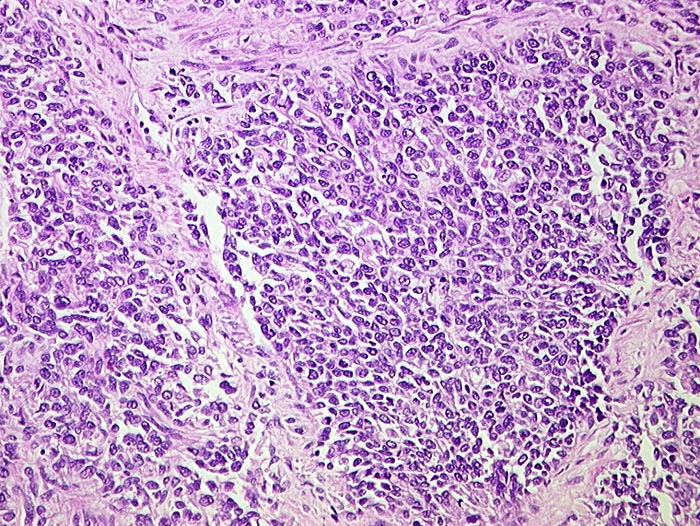

PathoPic ID 735 - Kleinzelliges Karzinom

Kleinzelliges Karzinom

maligner Tumor

Lunge

Solide Platten von kleinen Tumorzellen mit sehr wenig Zytoplasma und teils runden, teils eckigen Kernen.

Kleinzelliges Karzinom der Lunge als autoptischer Zufallsbefund. Lebermetastasen.

St.n. Radio/Chemotherapie wegen Hypopharynxkarzinom.

Histologie